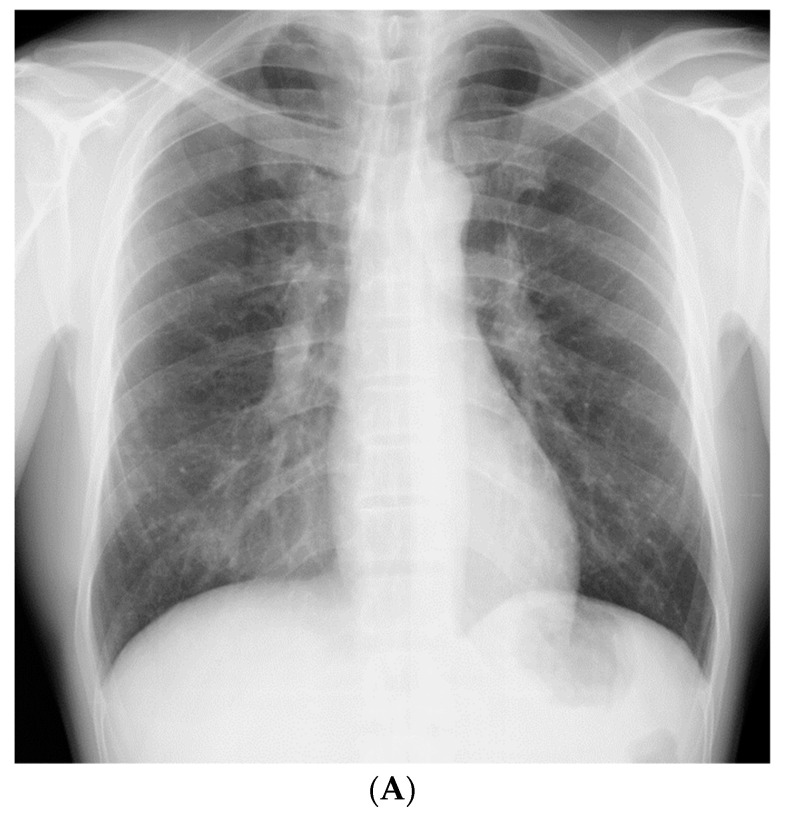

A 51-year-old, asymptomatic Japanese man with rapidly progressing nodular shadows, as observed on chest radiography performed as part of his routine physical examinations, was referred to our hospital. Two years ago, his chest radiograph had revealed no abnormalities. Small nodules had appeared a year later, mainly in both the lower lung fields (Figure 1A); however, he did not visit a hospital. Further, he reported a smoking history of 30 pack-years. As a civil engineer, he had been engaged in underground construction with welding, cutting, and drilling of reinforced concrete and metals for 10 years (between the ages of 41 and 51 years); though he had never used and/or been exposed to beryllium.

The patient did not display clinical respiratory symptoms such as dyspnea, exercise intolerance, or any other relevant manifestations upon referral to our hospital. The patient’s body temperature, pulse rate, and respiratory rate were 36.9 °C, 58 beats/min, and 20 breaths/min, respectively. On chest auscultation, fine crackles were audible in the bilateral lower lung fields. Clubbed fingers were not observed. Laboratory data on admission revealed elevated levels of PR3-ANCA (15.4 U/mL, cutoff level: 3.5 U/mL). Other representative tests for collagen disease-related autoantibodies were negative. Serum levels of angiotensin-converting enzyme, carcinoembryonic antigen, KL-6, and sIL-2R were in the normal range, and the results of interferon-gamma release assay were negative. The chest radiograph on admission showed an increase in the number of nodules compared with those found 1 year previously (Figure 1B).